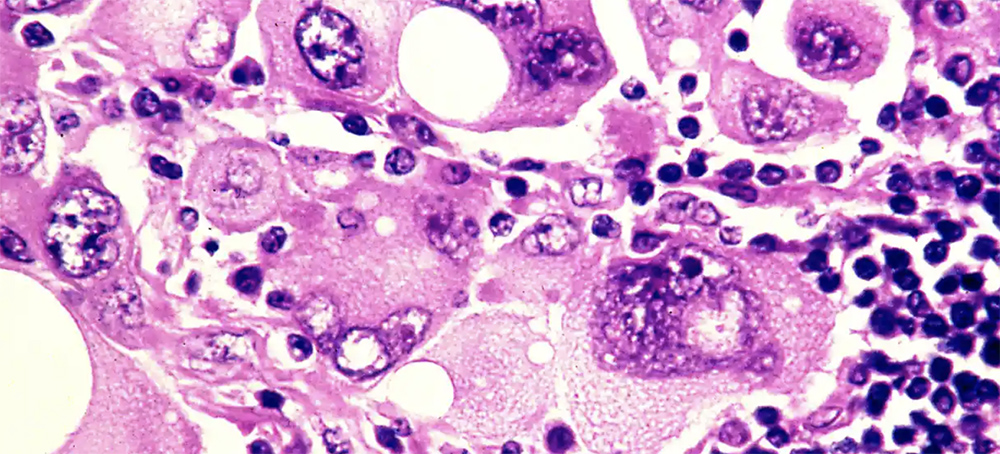

Photomicrograph of human metastatic melanoma cells. (photo: Phanie/Alamy)

Higher summer temperatures caused by climate crisis will lead to more cases of melanoma, say medics

“As a clinician treating patients with melanoma, I am definitely concerned that a sustained trend in hotter summers will lead to more cases of melanoma and more deaths from melanoma,” said Sarah Danson, a professor of medical oncology at the University of Sheffield.

Julia Newton-Bishop, a clinician scientist leading the melanoma research group at the University of Leeds, said: “Melanoma is caused essentially by sunburn, and this weather is so extreme that I am concerned that sunburns will increase and later so will the incidence of melanoma.”

According to data from Cancer Research UK, skin cancer death rates among men in the UK have more than tripled since the 1970s, with increases also recorded among women. It is thought the rise may be down to a number of factors including greater sun exposure due to package holidays, with Michelle Mitchell, the chief executive of Cancer Research UK, warning that getting sunburn just once every two years can triple the risk of skin cancer.